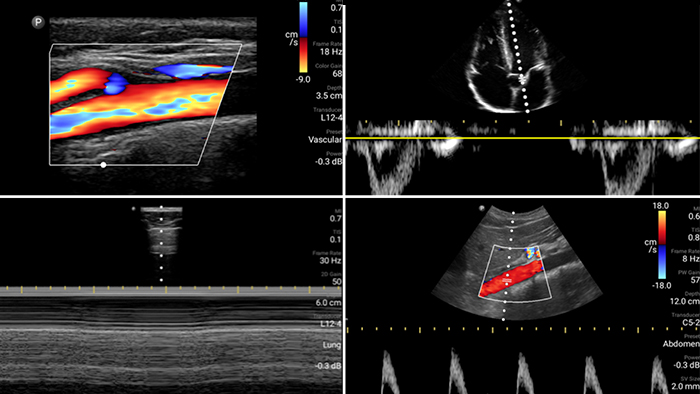

Evaluate, diagnose and treat your patients in minutes with a multi-point POCUS exam.

Lumify can help assess patients faster and improve accuracy when diagnosing common causes of dyspnea and other lung conditions.

• 4 to 1 MHz extended operating frequency range • 2D, color Doppler, M-mode, advanced XRES and multivariate harmonic imaging • High-resolution imaging for abdominal and cardiac applications: Cardiac, OB/GYN, Lung, Abdomen and FAST imaging preset optimizations Lumify aids life-saving technology in prehospital setting